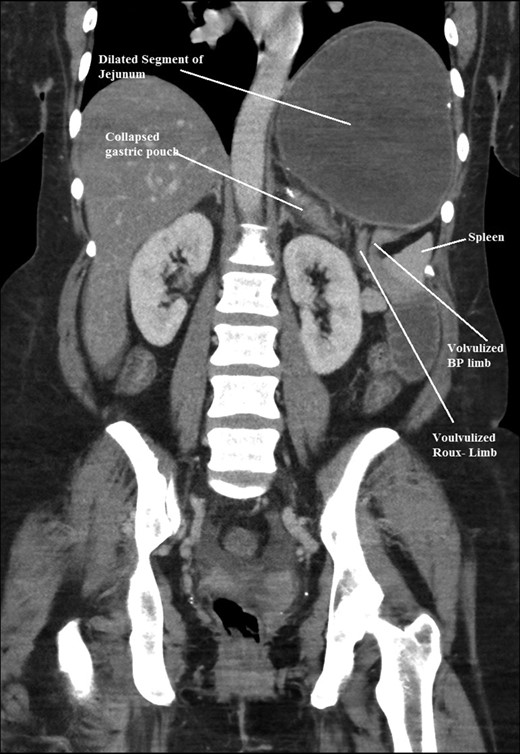

The intraoperative findings were not consistent with the radiological findings (Figs 1–4). As shown in the CT scan of abdomen and pelvis; multiple loops of dilated small bowel were seen, more predominantly dilated and matted bowel complex just above the spleen. The dilated bowel complex was decompressed using needle aspiration to help reduction of the bowel loops. The ileo cecal junction was then identified and traced back to the perisplenic hilar region. The trifurcation of three bowel loops (Roux limb, biliopancreatic limb and common limb) were identified with identification of ligament of Treitz. The prior gastric bypass was of ante colic- ante gastric type and Peterson’s defect was not closed. The above described bowel trifurcation had sunken postero- inferior to the spleen and had herniated through a potential space underneath the spleen and torsed around the splenic vessels and hilum. This picture was consistent with perisplenic small bowel volvulus. As noted earlier there was a massively dilated proximal small bowel segment above the spleen, displacing it caudally. Careful adhesiolysis was performed inferior to the spleen to release the segment of the trifurcation. The bowel segments once reduced were assessed and appeared viable. Of note, the spleen appeared better perfused after reduction. The remnant hernia defect of size 2 × 3 × 2.5 cm around the hilar region was then approximated using interrupted non-absorbable sutures. Enterotomy at the decompression site was closed with non absorbable suture. All potential sites of IH were re-examined and there was no evidence of any other internal herniation. Coelomic cavity was thoroughly irrigated and operation concluded successfully. Postoperative hospital stay was uneventful, and the patient was discharged home after two days.

Coronal CT scan of abdomen and pelvis showing volvulized bilio- pancreatic and Roux limbs within the obstructed segments in the splenic hilar region.

Coronal CT scan of abdomen and pelvis showing Volvulized segment of bilio-pancreatic limb and its mesentery in the spleen hilum.

Coronal CT scan of abdomen and pelvis showing Dilated jejunal segment causing caudad splenic displacement.